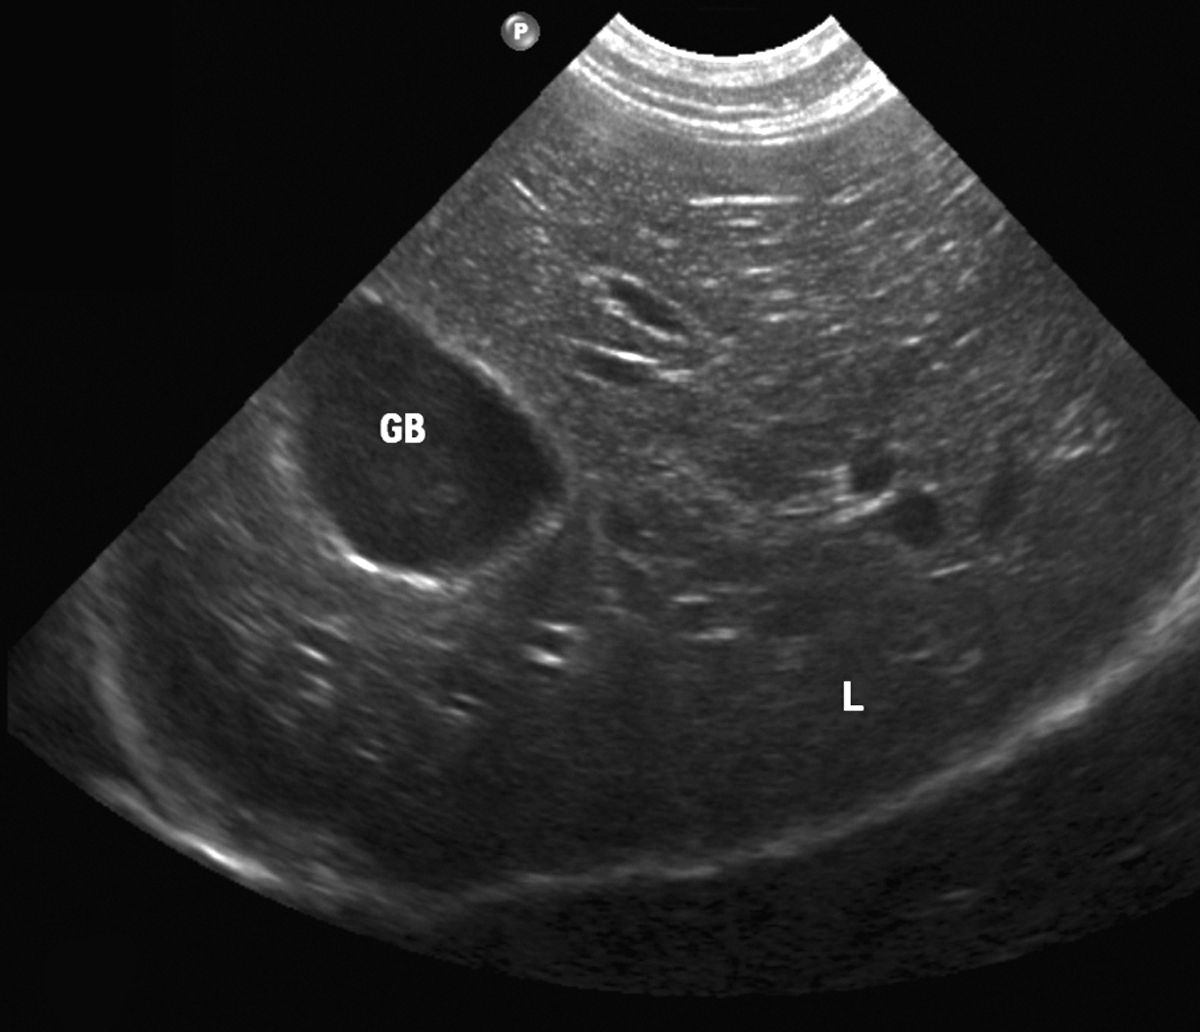

what does a healthy liver look like on ultrasound

Liver Ultrasound – Dr Iain Duncan

Normal ultrasound liver pattern. Echogenicity and echodensity of the …

Ultrasound of the liver, biliary tract, and pancreas | Abdominal Key

Imaging Studies of the Liver: Ultrasound